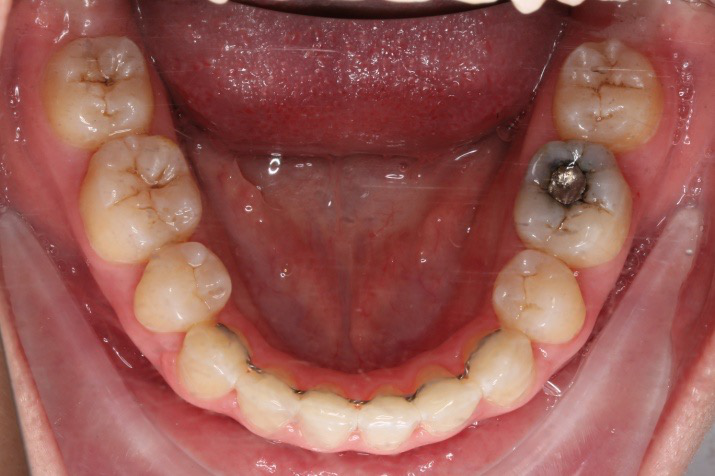

IntraoralExamination(2016-08.31,Wu)

• 磨牙,尖牙I类关系,中线齐

• 上下牙列中度拥挤

• 上下前牙唇倾

1.第0个月:2016.10.31 ◆ 初戴,0.013cu-niti